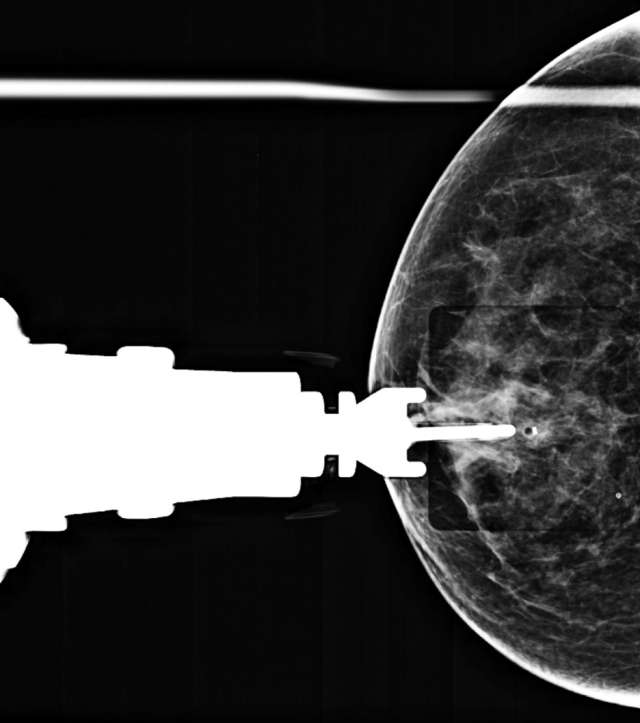

• Technologist takes single radiograph to demonstrate deployment of biopsy marker (Figure 6).

Figure 6. CC radiograph demonstrates post-biopsy changes and marker deployment.